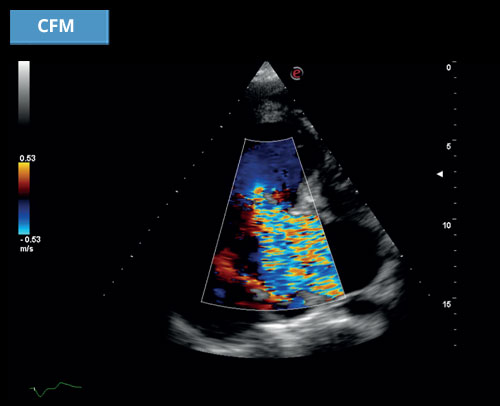

CFM

Lékaři v současnosti pravidelně používají různé technologie pro charakterizaci a diagnostiku patologie ve všech klinických aplikacích. Barevný Doppler, který pokrývá nejrůznější potenciální využití, představuje pilíř pro detekci jak vysokorychlostních toků, například v srdečních dutinách nebo ve velkých tepnách, tak i nízkorychlostních toků, například v malých a mikro cévách s dopplerem nebo bez něj.